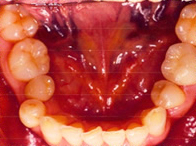

保険適用外の素材

術前![]()

術後